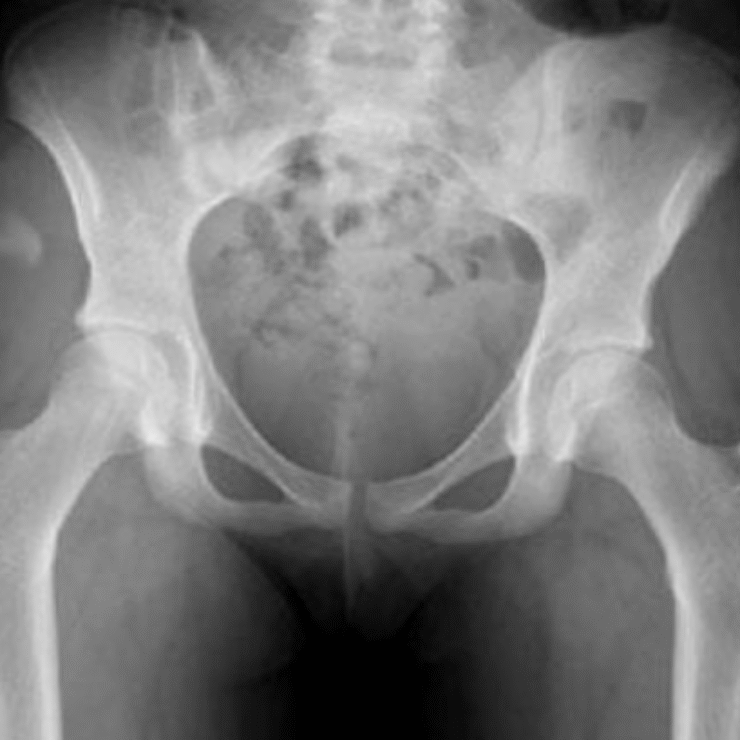

La hanche est l’articulation qui relie le bassin au fémur (os de la cuisse). Elle supporte le poids du corps et est essentielle au bon déroulement de la marche.

Le bassin est creusé d’une cavité arrondie appelée cotyle (ou acetabulum) dans laquelle s’articule l’extrémité supérieure sphérique du fémur appelée tête du fémur. Un joint appelé labrum, de consistance élastique assez ferme, coiffe le pourtour de la cavité et participe à la stabilité et la coaptation de l’articulation.